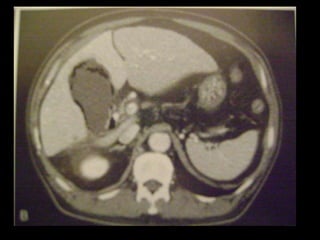

Colecistite Gangrenosa

Achados na TC:

Membranas intraluminais;

Hemorragia para o lúmen;

Parede irregular ou ausente;

Abscesso perivesicular;

Gás lúmen/parede.

Sensibilidade: 29,3%

Especificidade: 96%

Acurácia: 86,7%

Colecistite Gangrenosa Achados na TC: Membranas intraluminais; Hemorragia para o lúmen; Parede irregular ou ausente; Abscesso perivesicular; Gás lúmen/parede. Sensibilidade: 29,3% Especificidade: 96% Acurácia: 86,7%